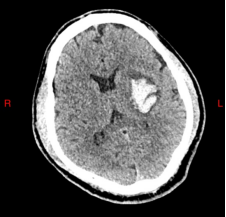

患者何先生(化名)因突发右侧偏瘫、失语紧急入院,CT显示其左侧基底节区脑出血量达20ml,病情危重。传统手术存在“盲穿”风险高、创伤大等问题,而红会医院神经外科别小华主任团队创新采用“可视导管+C臂CT导航”技术,实现全程可视化操作。

术前CT:清晰显示左侧基底节区20ml血肿

术中,团队通过导管内置高清摄像头精准避开血管,直达血肿中心,结合C臂CT实时导航动态调整穿刺路径,误差控制在1毫米以内。手术仅耗时30分钟,术后第3天患者语言功能明显恢复,右侧肌力显著改善,血肿清除率达95%。该技术的成功应用,标志着脑出血微创治疗迈入“精准、高效、安全”的新阶段。